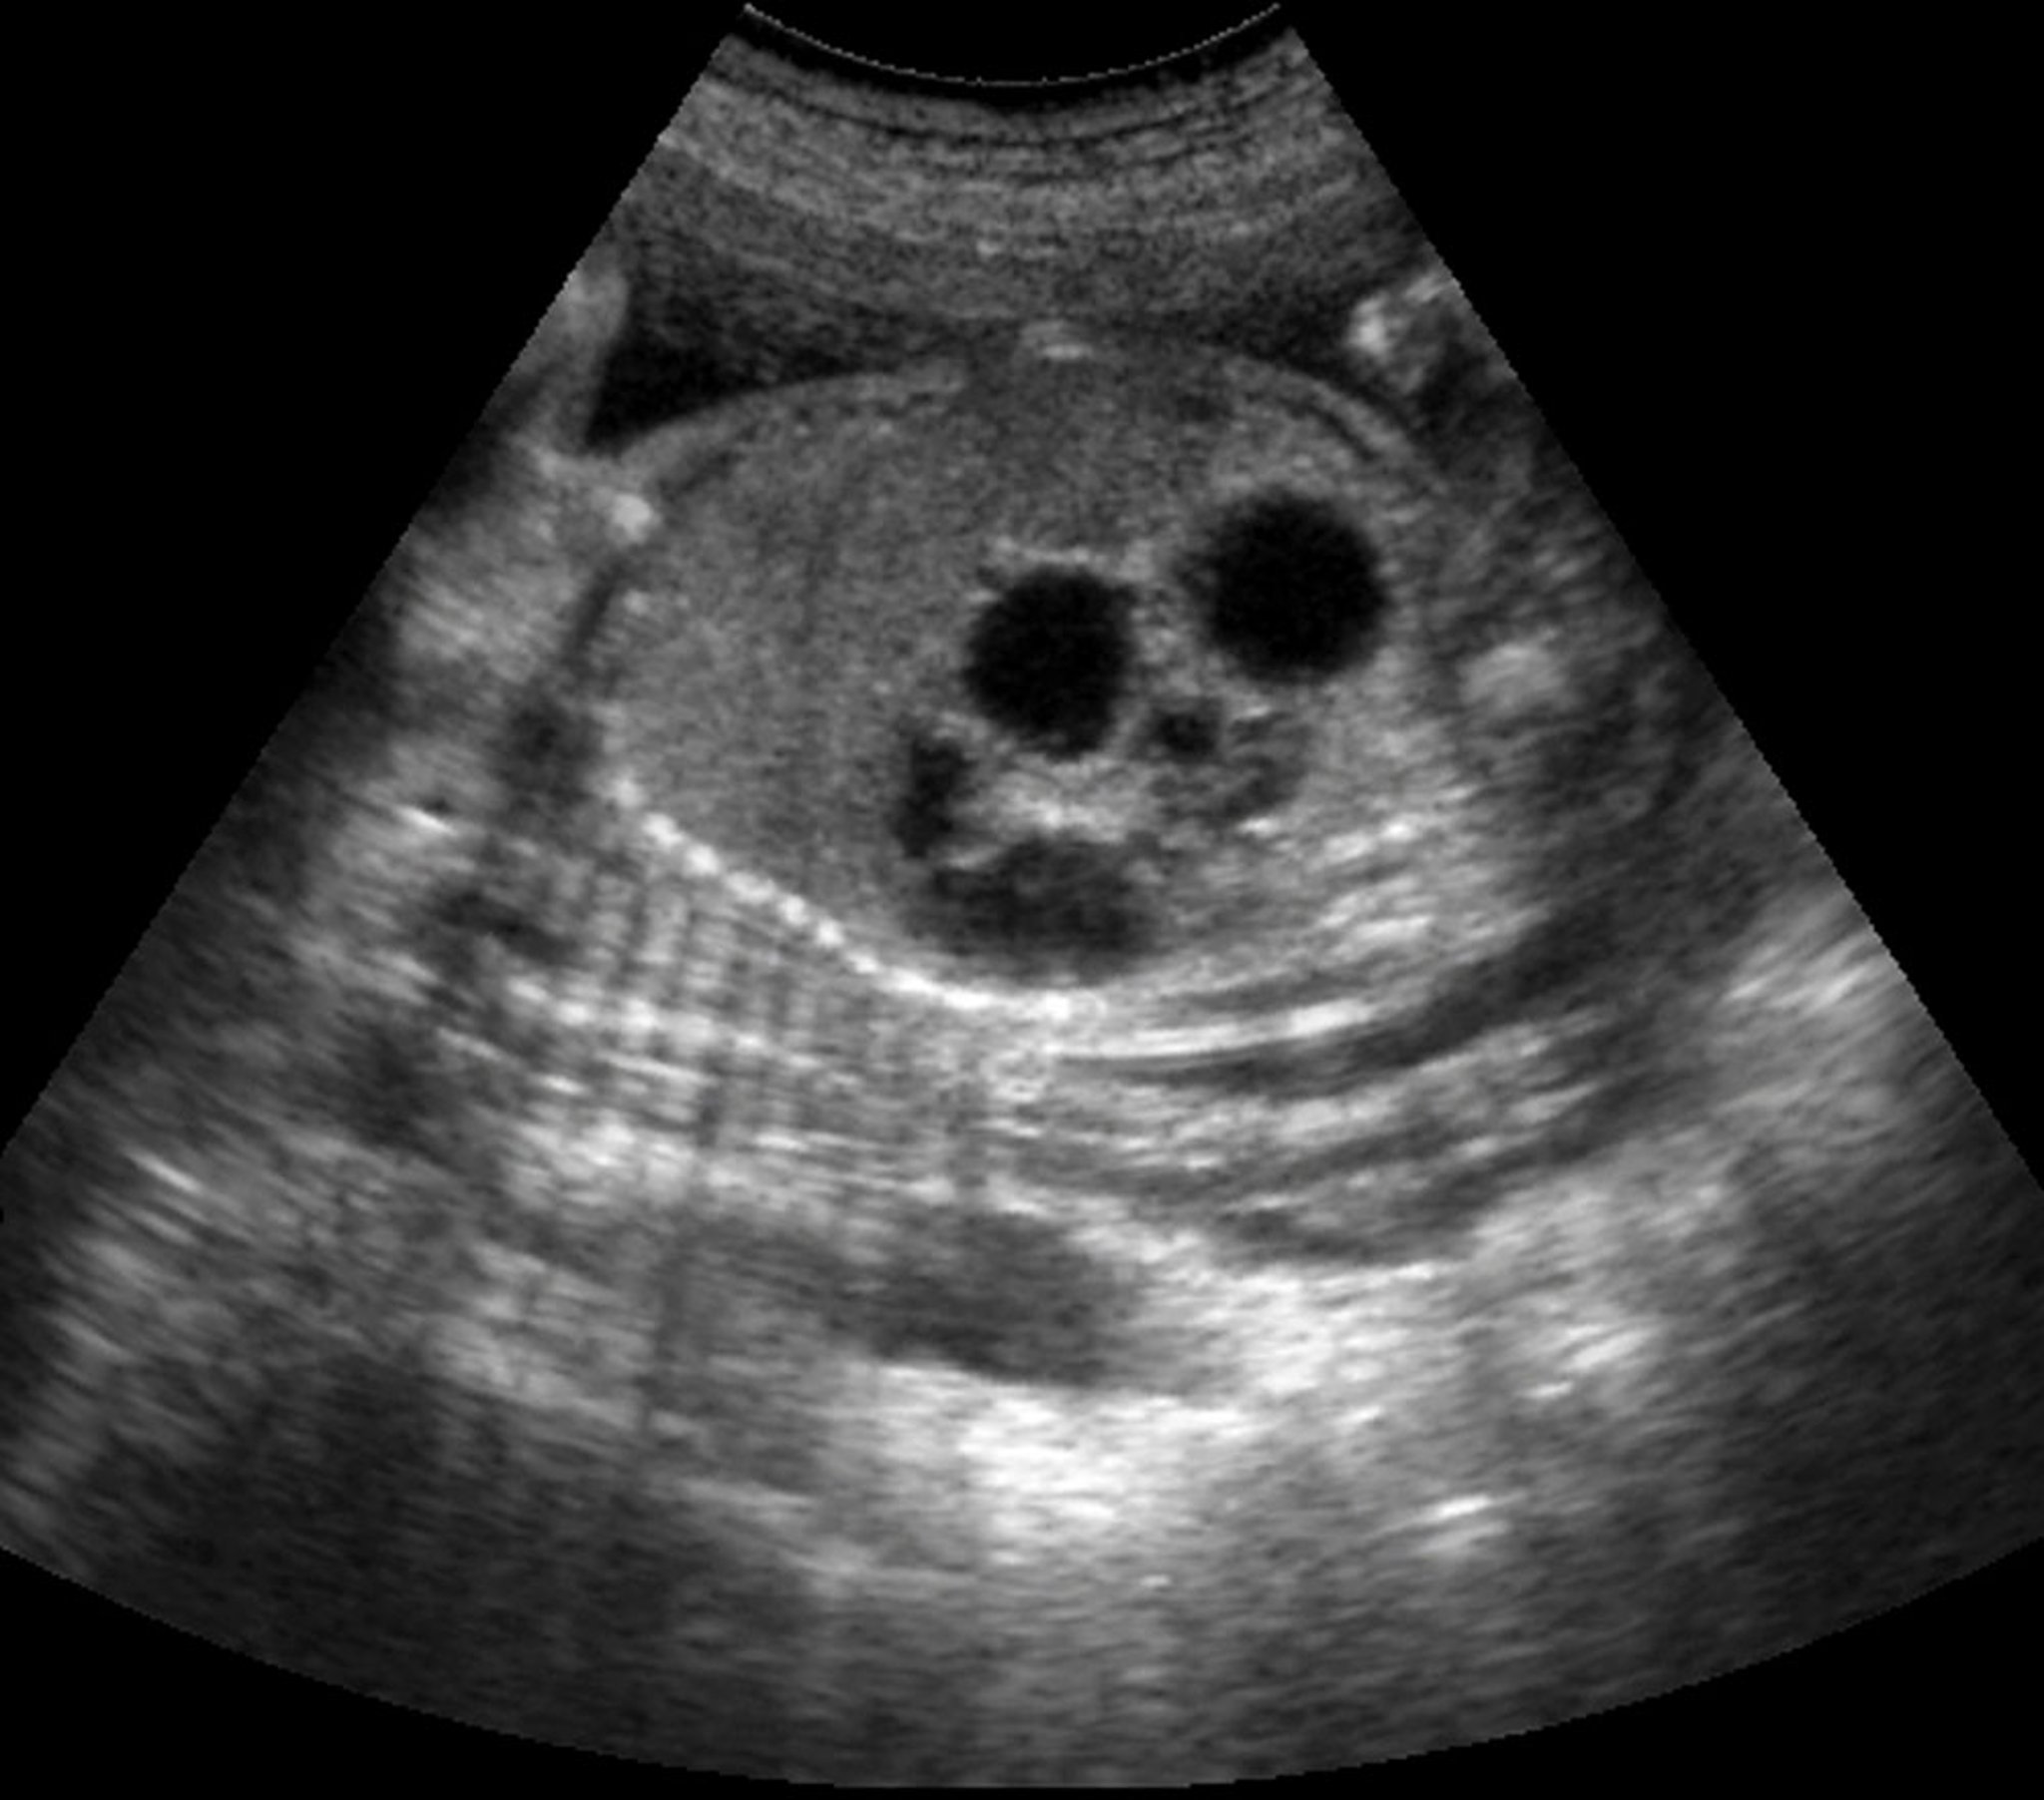

Diagnosis of duodenal atresia is suspected prenatally if there is polyhydramnios and/or a dilated stomach. Prenatal ultrasound can detect a double-bubble sign (a large gastric bubble and a smaller proximal duodenal bubble) in up to 80% of cases (2).

This ultrasound shows the double-bubble sign in a fetus with duodenal atresia.

This radiograph shows the typical double-bubble sign seen with complete duodenal obstruction. The smaller bubble represents the proximal, dilated duodenum (white arrow); the larger bubble represents the stomach (black arrow). This sign can be seen with duodenal atresia, duodenal web, annular pancreas, and preduodenal portal vein. Rarely, it can also be seen with complete duodenal obstruction resulting from Ladd bands in a patient with malrotation.